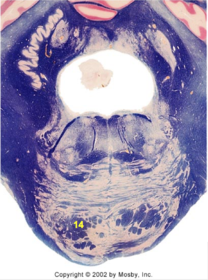

| Dorsal cochlear nucleus | |

| Inferior vestibular nucleus | |

| Medial vestibular nucleus | |

| Spinal nucleus of V | |

| Spinal tract of V | |

| Medullary pyramids | |

| Solitary nucleus | |

| ALS | |

| Medial lemniscus | |

| Medial longitudinal fasciculus | |

| Ventral cochlear nucleus | |

| Inferior olivary complex | |

| Inferior cerebellar peduncle | |

| CN IX | |

| Anterior spinocerebellar tract | |

| Central tegmental tract | |

| Olivary internal arcuate fibers | |

| Solitary tract | |

| Abducens root fibers | |

| Longitudinal pontine fibers (corticospinal tract) | |

| Transverse pontine fibers (dark fibers) | |

| Pontine nuclei (pale) | |

| Trapezoid body | |

| Ventral trigeminothalamic tract | |

| Superior olive | |